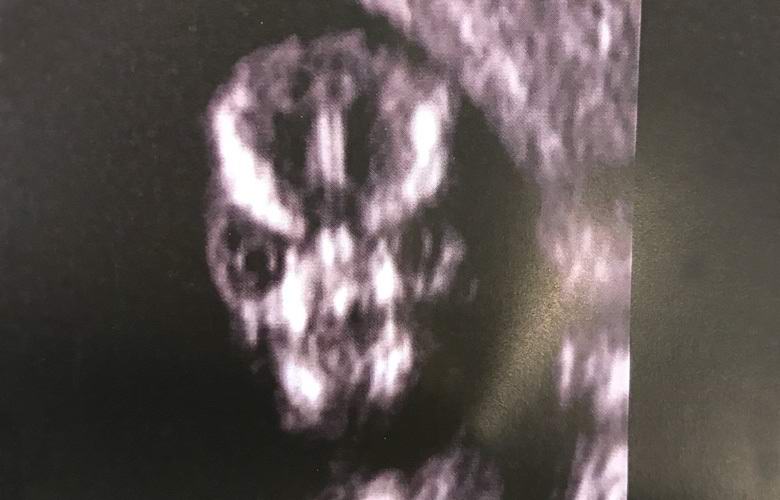

Raskaana oleva Sharney Turner vieraili sairaalassa sikiön sonografia ja huomasi kovan kasvot ultraäänilaitteen näytöllä, muistuttaa häntä joko kammottavasta hirviöstä tai muukalaisesta planeetta.

Tuleva äiti kysyi heti lääkäriltä, millaista kauhua. Lääkärit kuitenkin vakuuttivat naisen kertomalla hänelle kallo lapsella voi hyvinkin olla tämä ulkonäkö skannauksen aikana, ja ei syytä huoleen.

Ultraääni-asiantuntija päättää skannata kasvot poikani ja se osoittautui kammottavimmaksi asiaksi minä koskaan nähnyt elämässäni. Onko se todella inhimillistä näyttääkö kallo ultraääni? Mielenkiintoista, se on aina niin pelottavaa vai onko vain lapseni niin kauhea?

Monet Internet-käyttäjät olivat yhtä mieltä Turnerin kanssa siitä, että tilannekuva hänen syntymätön poikansa näyttää todella jotain Pelottavaa. Jotkut ei-niin-hyvät kommentaattorit jopa ehdotti, että sankaritarimme on raskaana antikristuksen tai mutantin kanssa. Kuten sanotaan, “vakuutti” naisen …